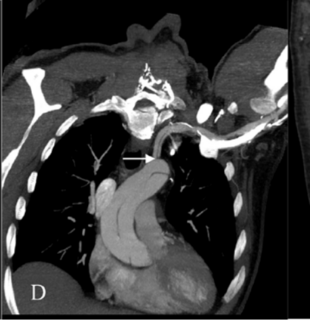

A 50-year-old man with a medical history of active smoking and diagnosed with type 2 diabetes mellitus was admitted to the ED complaining of sudden acute chest and left groin pain lasting 1 hour.